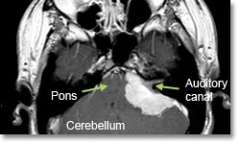

Location - Cerebellopontine angle (on the side of the brainstem)

Common Symptoms - Loss of hearing. Facial muscle weakness. Dizziness. Unsteadiness and incoordination, hydrocephalus (increased pressure inside the brain), voice and swallowing difficulties.

- Magnetic resonance imaging (MRI) scans effectively detect most meningiomas and are best at displaying details of the brain.